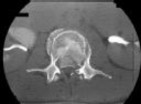

Figures 1 and 2 are CT scans obtained from a 68-year-old man who has had

progressive neck pain and stiffness, worsening gait imbalance, upper extremity weakness, early muscle fatigue, difficulty with fine motor control, and difficulty with activities of daily living over the past few years. On physical examination, he has a wide based stiff legged gait, generalized upper extremity weakness, dense sensory loss in the upper and lower extremities, and markedly brisk reflexes. What is the most appropriate treatment for this patient?

4. Posterior cervical laminoplasties from C3-6 Discussions: D

This patient has progressive myelopathy secondary to ossification of the posterior longitudinal ligament. Diagnostic imaging reveals multilevel cervical cord compression from C4-6. The patient has maintained reasonable cervical lordosis. A posterior procedure such as multilevel laminoplasty

decompresses the spine, is motion preserving, and has a low complication rate. Observation and cervical epidural injections are not viable options in patients with progressive myelopathy. Anterior cervical decompression, including corpectomy, is an option; however, anterior procedures have an increased risk of complications such as dural tear or cerebrospinal fluid leak. The axial CT image shows a "double layer" sign, which is consistent with dural ossification and increases the risk of dural injury with anterior decompression